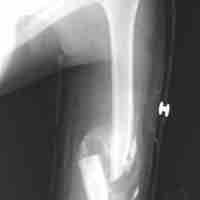

Bone Repair

Bone fractures are repaired through physiological processes in the periosteum via chrondroblasts and osteoblasts.